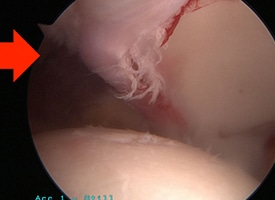

PRE OP

This arthroscopic photo demonstrates a labral tear.